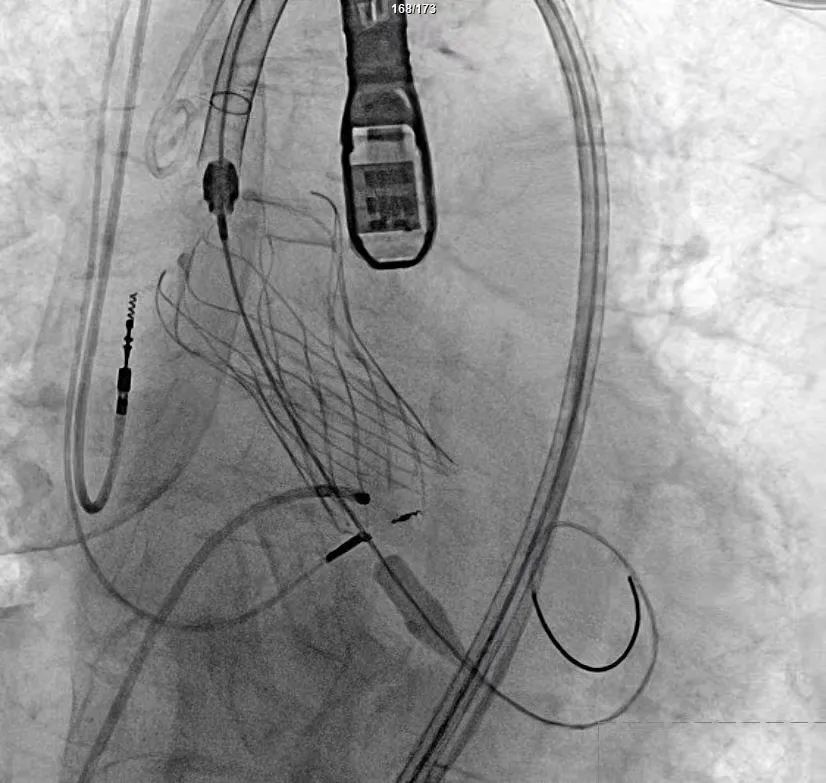

手术过程严谨有序:经术前精准评估与周密准备,团队成功送入预先装载的自膨式支架瓣膜输送系统,顺利完成过弓、跨瓣操作;经造影定位后,在180bpm快速起搏下精准释放瓣膜。瓣膜释放后,术中实时超声显示根部瓣架形态良好、启闭正常,瓣叶中心及瓣周未见反流;造影显示瓣膜位置满意、形态良好,冠脉显影清晰,入路血管无损伤,历经90分钟后,手术圆满成功。

术中影像